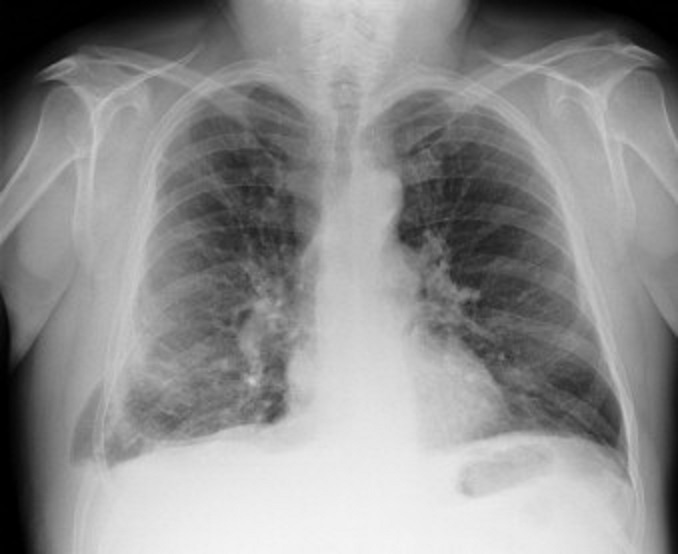

Image radiologique d'une hernie pulmonaire

parietale droit du poumon . Image hyperluscence

localisee à inferieure de partie molle de la paroi

du poumon droit . Cliche de face PA pulmonaire . |